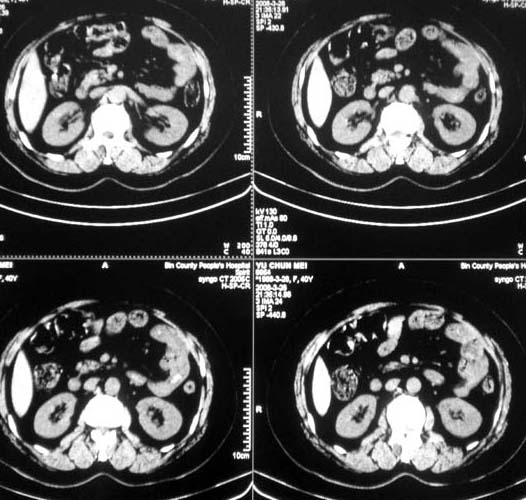

标题: CT12476:腹痛待查。

女,56岁,和上两个是同一病人,腹痛,胀痛,消化不良,五年前有血管瘤。密度减低影ct值为40hu。